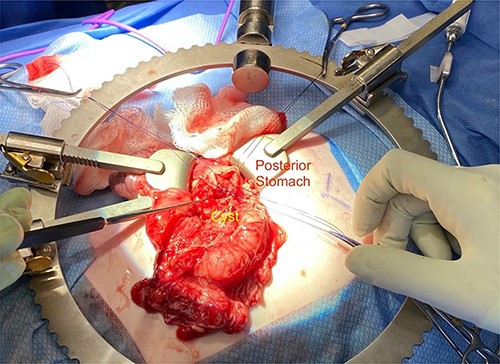

We noted that the patient had an annular pancreas; there was pancreatic tissue around D2 with no evidence of stenosis. There were dense adhesions between the posterior wall of the stomach and this mass, which was essentially embedded within the head of the pancreas and closely positioned but separate from the medial wall of D1 and posterior stomach. There was scarred inflammation extending along the transverse mesocolon, but no true fistula was seen (Fig. 2). There was no evidence of a connection to the pancreatic duct. An intraoperative ultrasound revealed a thick-walled cyst; the fluid in the cyst was of low density with areas of mucous debris dependently (Fig. 3).

Intraoperative image showing the duplication cyst in relation to surrounding organs, and the inflammatory tissue extending from the mass to the colon (at the tip of the forceps).

Given the location of the cyst, we felt resection would require a pancreaticoduodenectomy. Alternatively, because there was no biliary obstruction or evidence of chronic/recurring pancreatitis, it was safer to internalize the duplication cyst. The anterior cyst wall was opened, and its contents were about 2 ml of clear white fluid and a small amount of white mucous debris; samples were sent for culture and lipase, but unfortunately the amount of sample was not adequate for lipase. A mucosectomy (to mitigate the long-term risk of malignant transformation) and cystgastrostomy to the posterior antral wall were performed (Fig. 4). A Penrose drain was placed across the cystgastrostomy to maintain patency (Fig. 5).